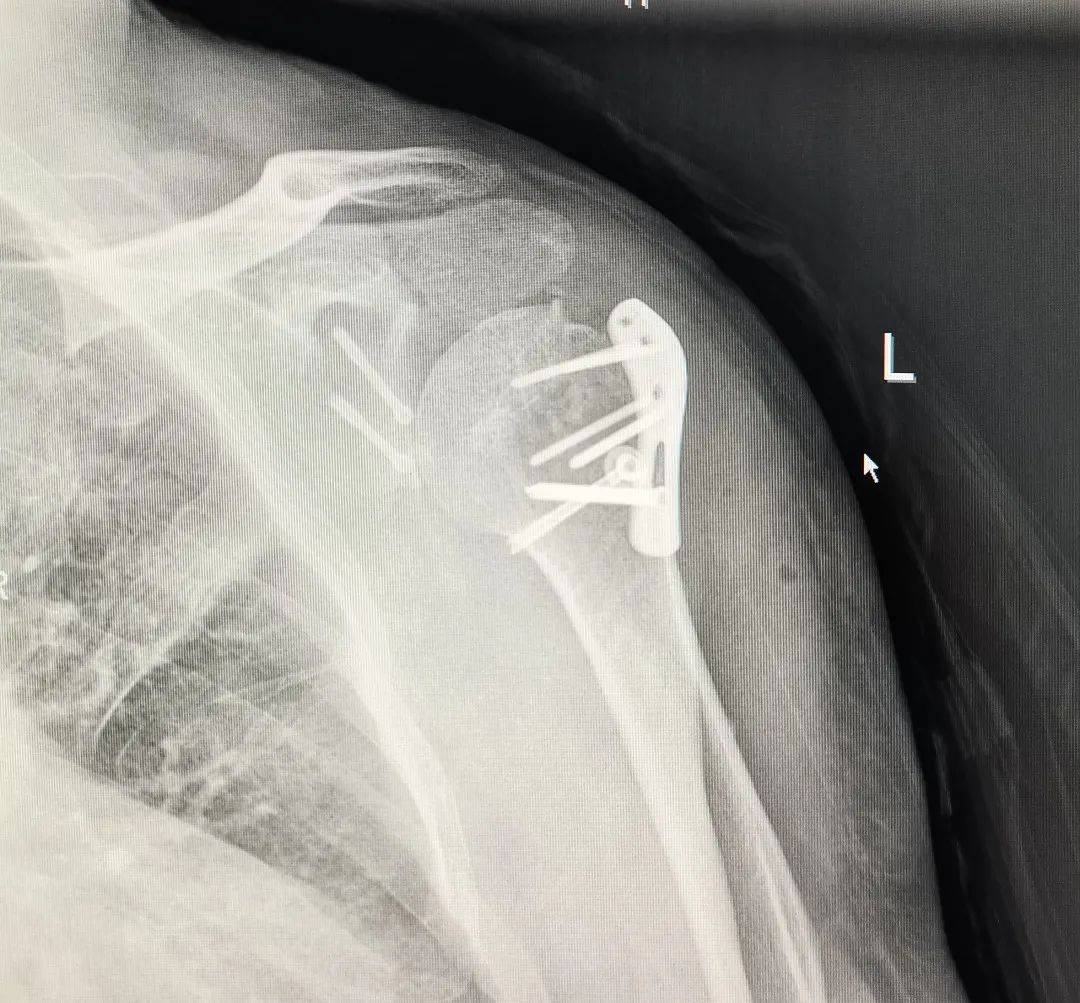

交通事故伤残鉴定需要拆除内固定吗?保持骨折的位置和稳定性,促进骨折愈合。很多经过内固定手术的当事人就会有一个疑问,我身体里面还有钢钉钢板,能带着内固定鉴定吗?还是说... 但需要注意的是,细则规定了四肢骨折邻近关节经内固定术治疗后,若依肢体关节活动受限程度可能评定为九级以上伤残者,须拆除内固定后进行...